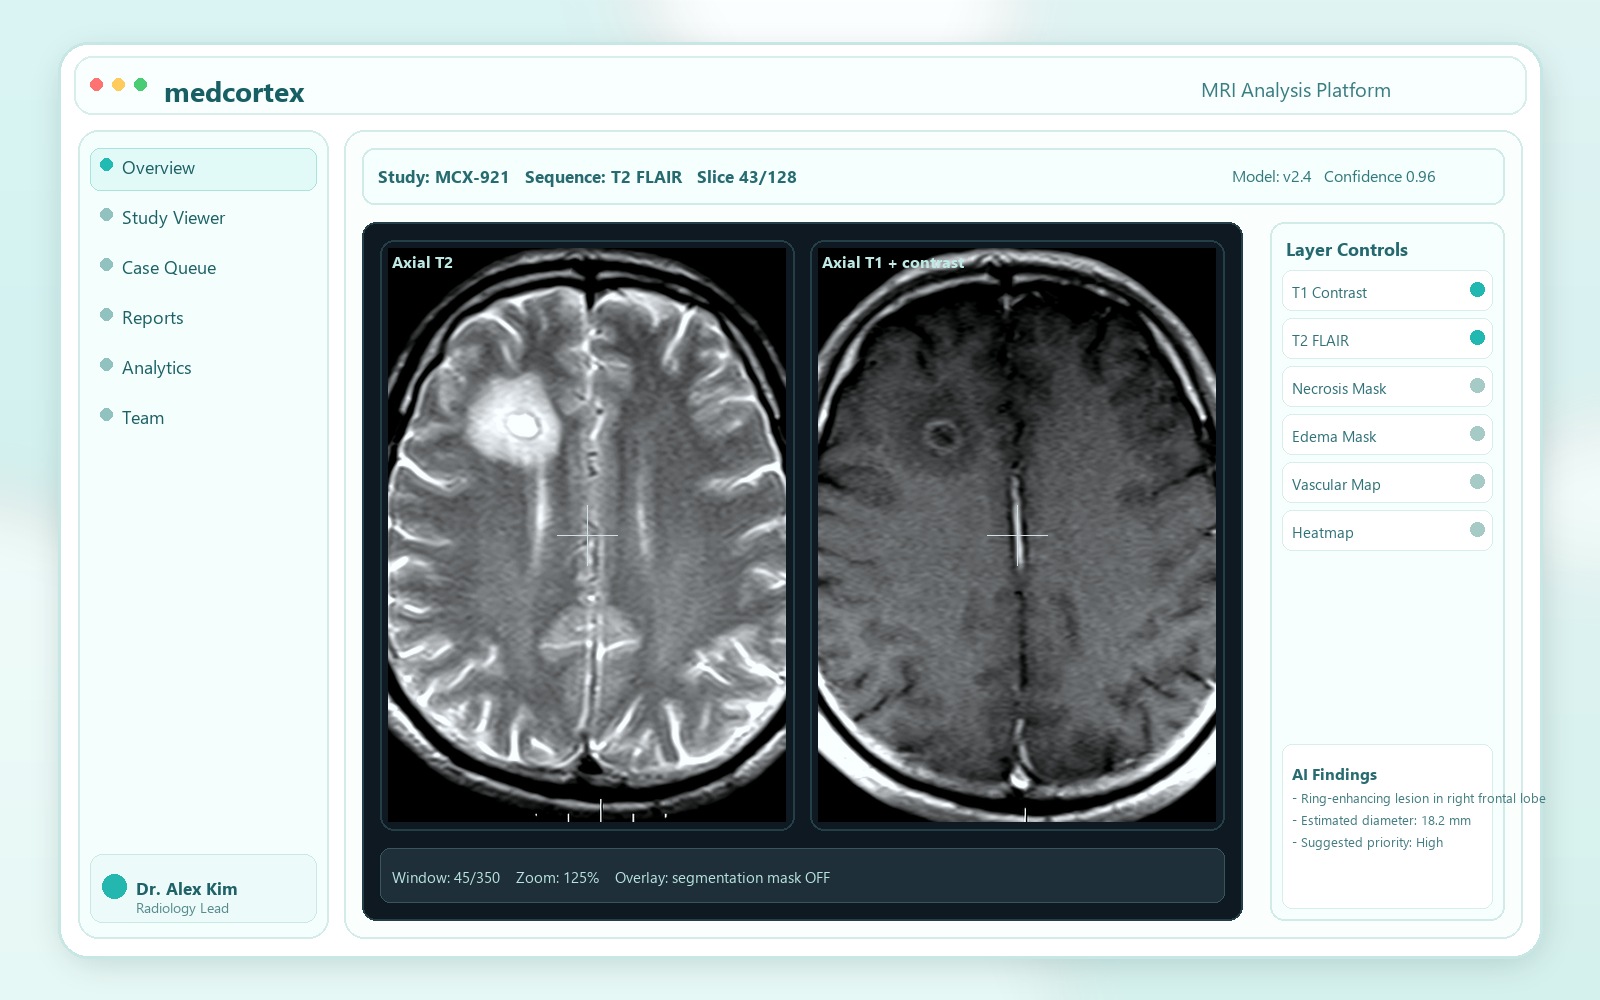

AI-powered MRI analysis for faster, clearer diagnosis support

Our in-house trained neural network highlights suspicious regions, quantifies change over time, and helps specialists prioritize urgent studies without disrupting existing workflows.